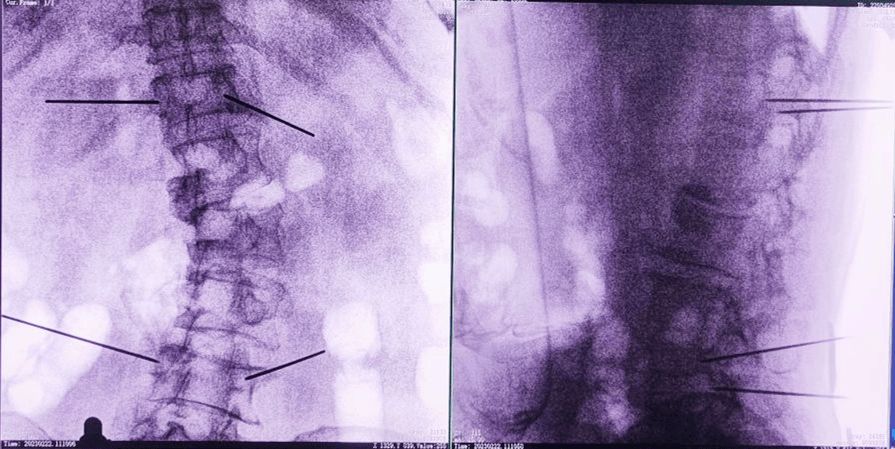

主任為患者注射骨水泥,再次影像掃描后,發(fā)現(xiàn)骨水泥進(jìn)入位置非常好,彌散效果更佳,手術(shù)順利完成,患者的恢復(fù)也自然更好。